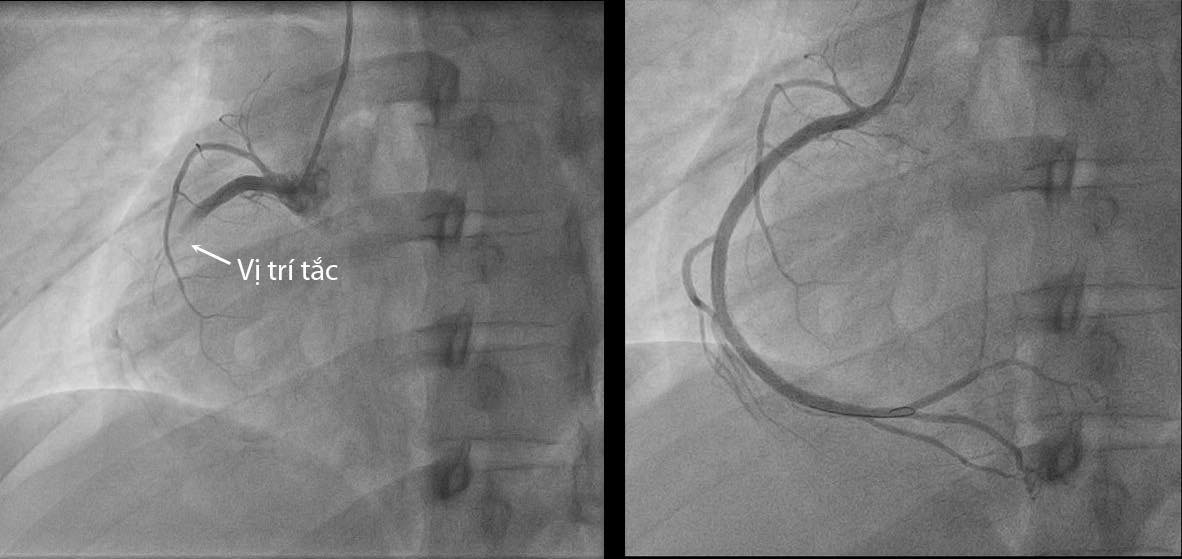

Kết quả chụp động mạch vành cho thấy bệnh nhân bị tắc hoàn toàn động mạch vành phải, lòng mạch có nhiều huyết khối. Bệnh nhân được can thiệp hút huyết khối và đặt stent để tái thông nhánh động mạch vành bị tắc, phục hồi dòng máu cung cấp cho cơ tim.